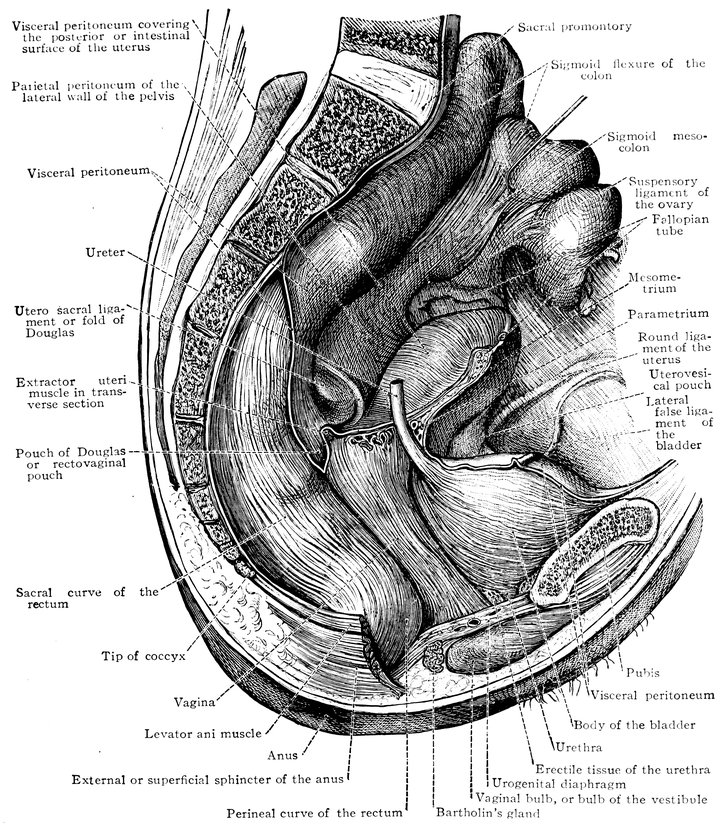

Fig. 2.—Portion of the pelvic viscera in the female, and their relation to the muscles of the pelvic outlet (or perineal muscles), shown in the left half of the pelvis, seen from the right side.—The parametrium. (From Toldt: Atlas of Human Anatomy.—Rebman Company, New York.)